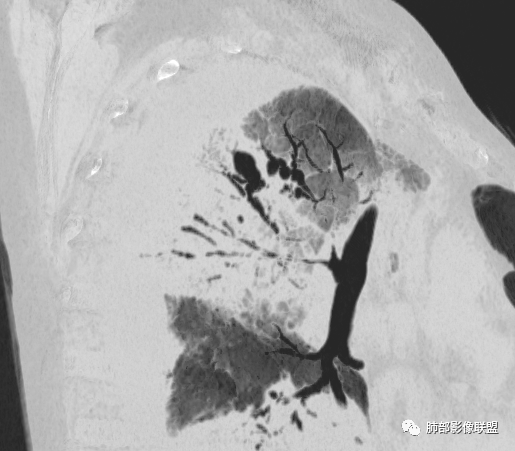

出院前复查CT:

该病例,需要二元解释,这么高的白细胞提示感染,这个病例确实很怪。一是感染,还有淋巴瘤,一直在犹豫远端的空腔还是扩张支气管,如何形成的。这个看支气管及远端的泡。

如果支气管看通透了,估计会朝二元论考虑。这个病例好,值得好好总结。

从支气管的改变:要警惕淋巴瘤。左肺病变沿支气管血管束分布,支持间质为主病变。

复查左肺病灶没好转

也不符合急性炎症特点

还有一次CT:

这也是我判断失误的原因之一:树芽征

重建后就是血管束增粗

我以为树芽征,其实是中轴间质增厚

没看清楚,只看到表面,考虑小气道结节,那些是支气管扩张+空洞,所以考虑结核,其实两点都错了,谢谢赖老师。

应该要二元.看这样的支气管。